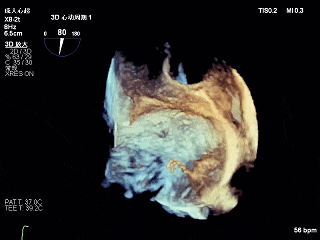

3D-ZOOM 彩色多普勒显示反流主要来源于2区

考虑到患者的反流机制为FMR,主要由于瓣环扩张引起瓣叶对合不良导致二尖瓣重度反流,心衰等问题,且二尖瓣瓣叶质量长度尚可,患者年龄较小,综合考虑决定在2区反流最重位置植入第一枚XTR后观察反流情况,决定是否”side by side”植入第二枚XTR。